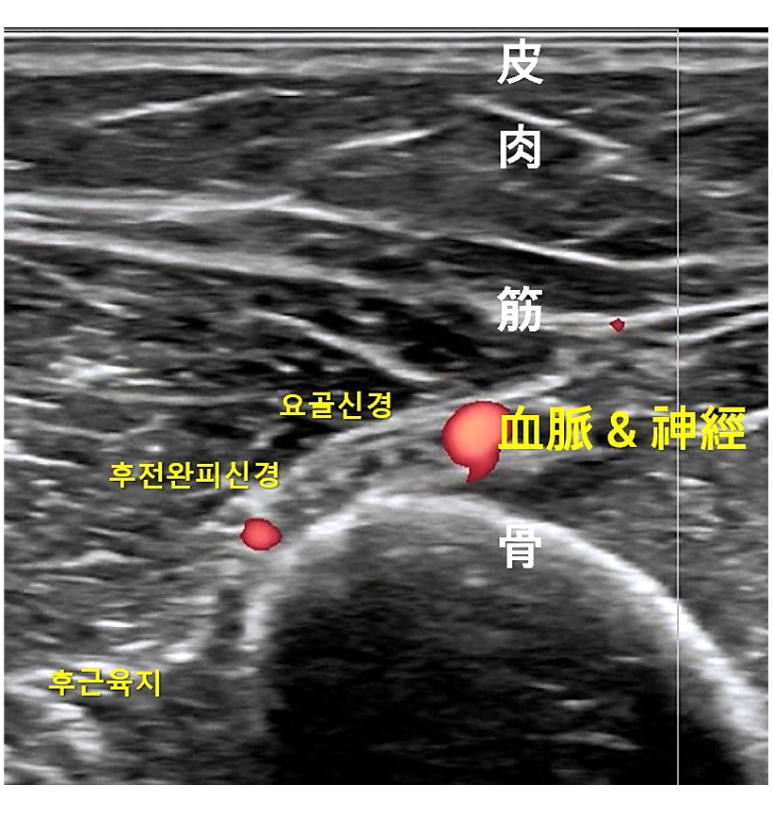

위 그림은 제가 소락혈을 초음파로 관찰한 영상입니다. 소락혈 심부에는 요골신경과 심부상완동맥 뿐만 아니라 후완전피신경이나 삼두근을 지배하는 후근육지도 함께 보입니다. 이렇게 신경과 혈관이 밀집된 고위험 부위에 시술할 때는 초음파가 굉장히 유용하거든요. 물론 일반침은 매우 안전해서 굳이 초음파를 쓸 필요가 없어요. 하지만 약침, 도침 같은 특수침 치료에 초음파를 결합하면 안전성과 유효성을 더욱 높일 수 있기에 잘 낫지 않은 만성 질환들은 초음파를 활용하는 것이죠.

약침을 시술하기 전에 먼저 손끝 감각으로 혈자리를 확인한 후, 그 자리에 그대로 초음파 프로브를 대어 신경, 혈관 등의 고위험 구조물을 확인합니다. 소락혈 주변에서 민감한 통증이 재현되는 아시혈을 찾아서 약침을 시술하는 영상입니다. 이렇게 경근 초음파를 활용한다면 동맥과 신경을 피해서 정확하게 시술할 수 있습니다.